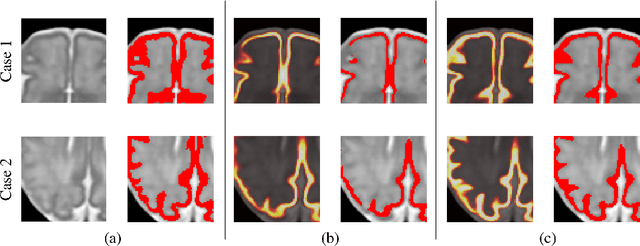

Abstract:The fetal cortical plate (CP) undergoes drastic morphological changes during the in utero development. Therefore, CP growth and folding patterns are key indicator in the assessment of the brain development and maturation. Magnetic resonance imaging (MRI) offers specific insights for the analysis of quantitative imaging biomarkers. Nonetheless, accurate and, more importantly, topologically correct MR image segmentation remains the key baseline to such analysis. In this study, we propose a deep learning segmentation framework for automatic and morphologically consistent segmentation of the CP in fetal brain MRI. Our contribution is two fold. First, we generalized a multi-dimensional topological loss function in order to enhance the topological accuracy. Second, we introduced hole ratio, a new topology-based validation measure that quantifies the size of the topological defects taking into account the size of the structure of interest. Using two publicly available datasets, we quantitatively evaluated our proposed method based on three complementary metrics which are overlap-, distance- and topology-based on 27 fetal brains. Our results evidence that our topology-integrative framework outperforms state-of-the-art training loss functions on super-resolution reconstructed clinical MRI, not only in shape correctness but also in the classical evaluation metrics. Furthermore, results on additional 31 out-of-domain SR reconstructions from clinical acquisitions were qualitatively assessed by three experts. The experts' consensus ranked our TopoCP method as the best segmentation in 100\% of the cases with a high inter-expert agreement. Overall, both quantitative and qualitative results, on a wide range of gestational ages and number of cases, support the generalizability and added value of our topology-guided framework for fetal CP segmentation.

Abstract:The fetal cortical plate undergoes drastic morphological changes throughout early in utero development that can be observed using magnetic resonance (MR) imaging. An accurate MR image segmentation, and more importantly a topologically correct delineation of the cortical gray matter, is a key baseline to perform further quantitative analysis of brain development. In this paper, we propose for the first time the integration of a topological constraint, as an additional loss function, to enhance the morphological consistency of a deep learning-based segmentation of the fetal cortical plate. We quantitatively evaluate our method on 18 fetal brain atlases ranging from 21 to 38 weeks of gestation, showing the significant benefits of our method through all gestational ages as compared to a baseline method. Furthermore, qualitative evaluation by three different experts on 130 randomly selected slices from 26 clinical MRIs evidences the out-performance of our method independently of the MR reconstruction quality.